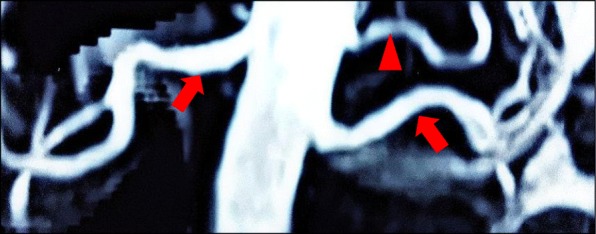

Fig. 2.

Renal MRA. MR angiography of the renal arteries in a 40-year-old woman with hypertension and secondary hyperaldosteronism demonstrating a nonstenotic left accessory renal artery. (Arrowhead = accessory renal artery; closed arrow = main renal artery)

A 41 year old lady with history of hypertension for 3 years treated with amlodipine 5 mg daily, presented with body weakness for a week and difficulty climbing stairs for a few months. She did not have any prior gastrointestinal losses and denied the use of traditional medications. Investigation done showed hypokalemia at 1.8 mmol/L and she was hospitalized. On examination, blood pressure was 145/100 mmHg with pulse rate of 85 per minutes. Her BMI was 30.5 kg/m2 but she did not appear cushingnoid. There was no abdominal bruit. Physical examination was otherwise unremarkable. Investigation showed normal thyroid function, renal function and normal serum calcium and magnesium. There was metabolic alkalosis with serum bicarbonate of 32 mmol/L. Cortisol after overnight 1 mg dexamethasone suppression was normal at 0.69 μg/dl. Hypertension was controlled with diltazem 30 mg tds but she required oral potassium chloride at 1.8 g tds to maintain normal potassium level. Serum aldosterone was 1046 pmol/L with plasma renin of 6.5 ng/ml/hour (reference range 0.2–2.8) giving an ARR of 161. Her echocardiogram was normal with no left ventricular hypertrophy or coarctation of aorta. Renal Doppler showed prolonged acceleration time of the left renal artery with spectral widening. Peak systolic velocities and resistive indices within normal limits but findings were suspicious for left renal artery stenosis. MRA of the kidneys revealed normal kidneys and normal main renal artery calibers bilaterally. However a small accessory left renal artery was seen 1 cm above the origin of the left main renal artery supplying the upper pole (Fig. 2). There was no stenosis detected in the accessory artery. Her blood pressure and hypokalemia were controlled with spironolactone 50 mg daily and oral potassium chloride 1.2 g daily.